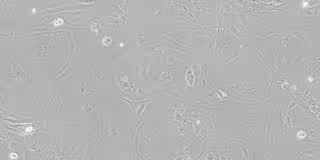

Células epiteliales del timo derivadas de células iPS, visualizadas por microscopía de contraste de fase.

Células epiteliales del timo derivadas de células iPS, visualizadas por microscopía de contraste de fase. - HOKKAIDO UNIVERSITY

Investigadores de la Universidad de Hokkaido (Japón) han descubierto que las células del epitelio del timo derivadas de las células madre pluripotentes inducidas (iPS) de ratones pueden regular la respuesta inmunológica a los injertos de piel, prolongando su supervivencia.